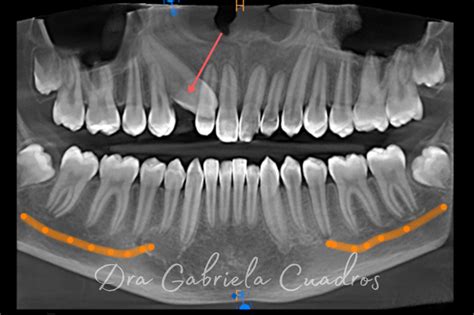

En la radiografía panorámica observamos canino superior derecho retenido, segundos molares permanentes superiores e inferiores en vía de erupción y terceros molares inferiores incluidos.